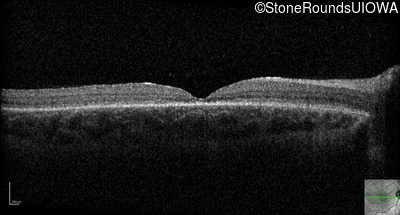

Optical Coherence Tomography - Right - 20/100 -1 sc

Exemplar / OCT Stack

OCT Stack